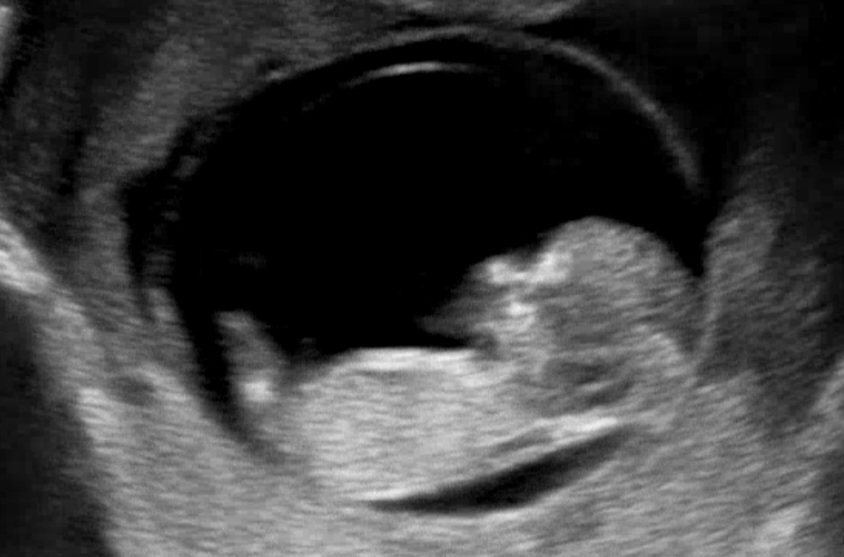

각도법!? 울 아가도 봐주세요ㅠㅠ

너무나 궁금한데 저는 아무리 봐도 모르겠더라구요ㅠㅠ 11주 초음파사진인데 아직 구분을 못...하는게 맞는건가요?ㅎㅎ 너무 궁금하네요❤️